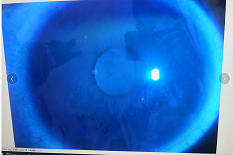

圓錐角膜要做那種治療比較好

【文章導(dǎo)讀】圓錐角膜的治療應(yīng)該依據(jù)角膜發(fā)展的時期選擇。目前圓錐角膜按照臨床癥狀大致可以分為四個時期,分別為潛伏期、初發(fā)期、完成期和瘢痕期,各個時期的主要癥狀表現(xiàn)如下: 潛伏期:

圓錐角膜的治療應(yīng)該依據(jù)角膜發(fā)展的時期選擇。目前圓錐角膜按照臨床癥狀大致可以分為四個時期,分別為潛伏期、初發(fā)期、完成期和瘢痕期,各個時期的主要癥狀表現(xiàn)如下:

潛伏期:癥狀不明顯。

初發(fā)期:開始近視,同時散光和不規(guī)則散光度數(shù)也會逐漸增加。

完成期:發(fā)展迅速,角膜明顯前突,視力銳減。

瘢痕期:角膜急性角膜水腫、混濁,消退后基質(zhì)層殘留瘢痕。

對于對于進展非常慢,可能幾年曲率都不變化的圓錐角膜,可以觀察隨診,或者佩戴RGP矯正。如果角膜發(fā)展較快,近視散光度數(shù)增加較快,則需要通過角膜交聯(lián)來治療。

圓錐角膜的形成機制就是膠原變薄,變?nèi)?。圓錐角膜患者的角膜膠原變薄了以后,彈性增加,正常的眼壓會使角膜向前膨隆。

角膜膠原交聯(lián)手術(shù)可以通過藥物,維生素B2和紫外線交聯(lián),使角膜里面的膠原纖維的硬度增加,在對抗正常眼壓情況下,對抗力增加。交聯(lián)后角膜的韌度增加,就不容易再往前繼續(xù)發(fā)展。

但如果已經(jīng)發(fā)展到圓錐后期,再去交聯(lián)就沒有意義,就只能通過角膜移植手術(shù)治療,把向前凸起的角膜給切掉,換成新的角膜。

目前圓錐角膜的治療方式主要就是配鏡矯正、角膜膠原交聯(lián)手術(shù)以及角膜移植手術(shù)這幾種。